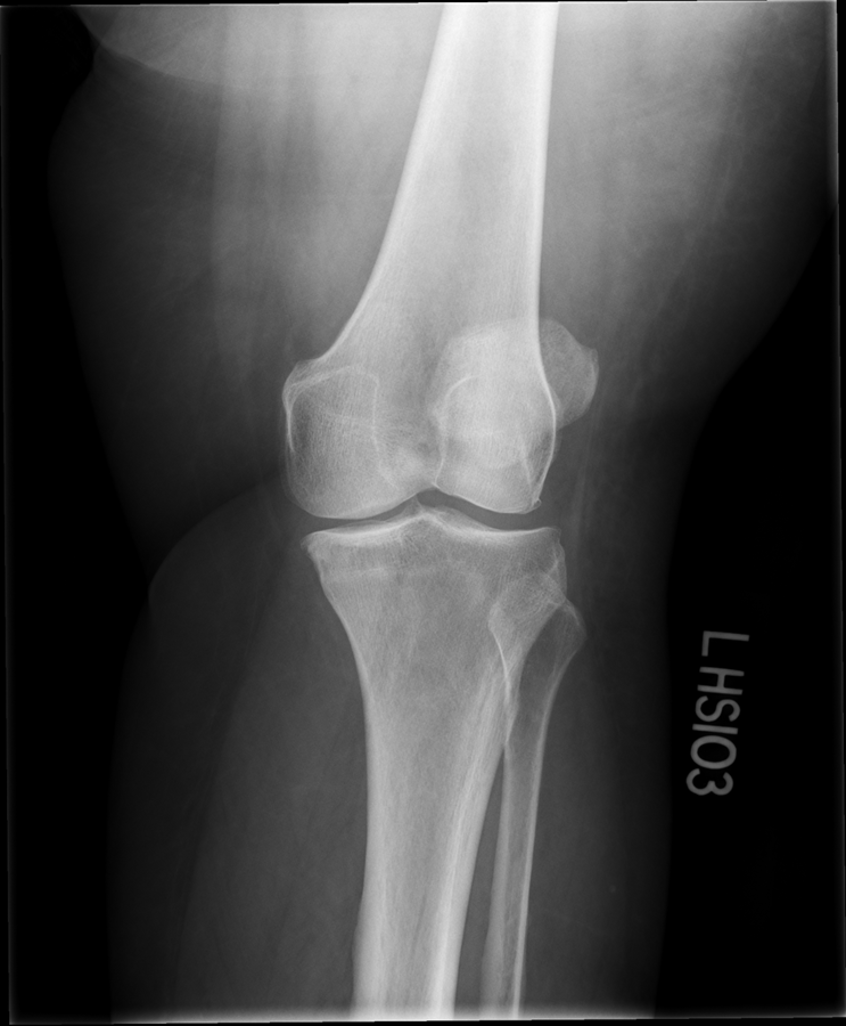

osteoarthritis (degenerative joint disease)

generalized disorder pathologically characterized by loss of joint cartilage & reactive new bone formation

traumatic, stress to joint

what is the casue of osteoarthritis?

advance stage → subtractive disease

pt w/ osteoarthritis

what is this image?